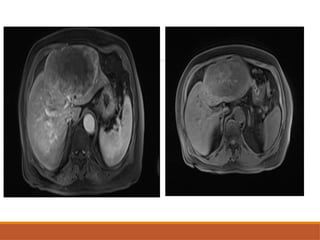

• #38 Axual cect image of fcc showing a large lesion in the right lobe, heterogeneously enhancing in the arterial phase, with more homogenous enhancement in the portal venous phase. The central part of the lesion appears to be non enhancing – likely scar site

• #40 Axial mr images showing a Large well defined heterogenous mass in the left lobe of liver, No diffusion restriction largely only rim enhancement with washout and persistent delayed enhancement of the capsule with large non enhancing central necrosis. No synchronous lesion. No background hepatic cirrhosis.